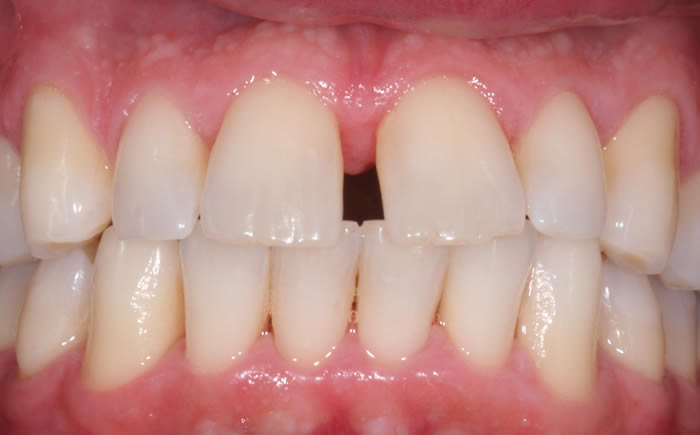

Front teeth replaced by dental implants

Missing upper front tooth replaced by dental implant and crown